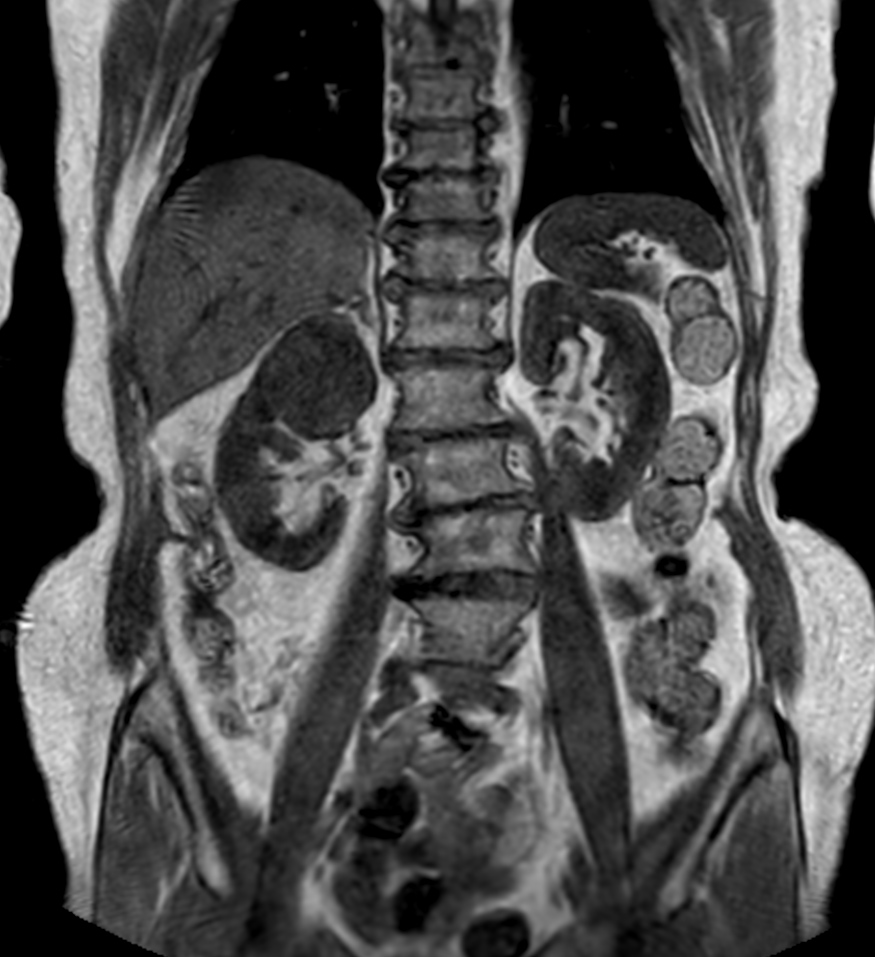

Patient with a kidney lesion. The ExamCard includes techniques for 3D imaging (PelvisVIEW, eTHRIVE) allowing for multiple image directions in one single scan, efficient fat-free imaging over large field-of-views (mDIXON XD), a multi-phase contrast-enhanced sequence (4D FreeBreathing) to improve imaging confidence and Compressed SENSE to accelerate the entire exam.

T2w TSE